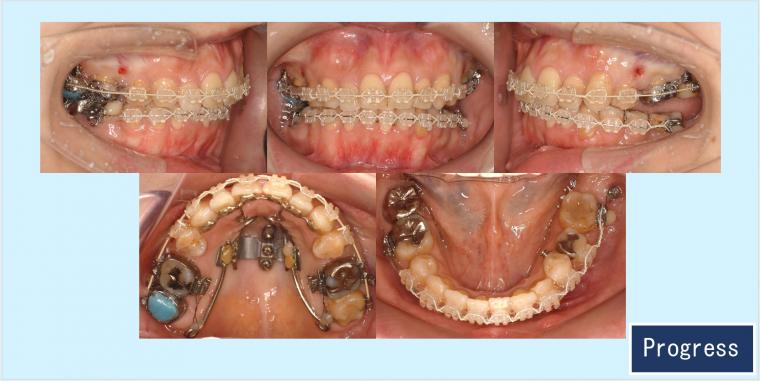

歯科矯正用アンカースクリュー植立を口蓋部(i-station)と歯槽部に併用して、抜歯スペースを利用して上下顎の叢生や上顎歯列全体の圧下による下顎のオートローテーションを致しました。咬合はもちろんですが、口元・側貌・スマイルラインとてもきれいになりました。

治療に用いた主な装置:

◎上顎 セラミックラビアルブラケット矯正装置

◎歯科矯正用アンカースクリュー 口蓋型(i-station)歯槽部TAD併用

抜歯部位:上顎両側5番、下顎右側5番と下顎左側6番